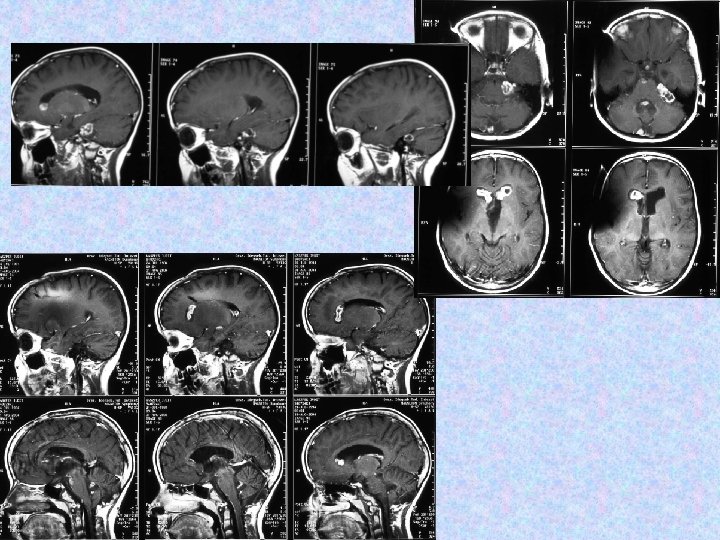

• 1998. június 30 -án jobb oldali VP shunt került behelyezésre. Biopsziát későbbre terveztek. • 1998. július 20 -án készült CT beszűkült szupratentoriális kamrarendszert mutat. A shunt jó pozícióban helyezkedik el. • Az 1998. augusztusi MRI nem mutat progressziót sem a kraniális, sem a spinális folyamatokban. • Az 1998. december 7 -i MR felvétel progressziót mutat. Neurológiailag a betegnek kétoldali Babinski tünetei, élénk mélyízületi reflexei vannak, izomzata hypotoniás. Egyebekben negatív státusz. A shunt közepes nyomás mellett jól vezet.

• 1998. december 10 -én arachnoideális biopszia történt szuboccipitális kraniotómiából, ami meningeális gliomatózist igazolt alacsony proliferációs indexszel. Szövettanilag pilocitás asztrocitóma igazolódott. Komplikáció, neurológiai novum nem lépett fel. A disszemináció miatt sugárterápia javasoltak az egész koponyára és gerincre. • A gyermek kemoterápiában részesült 1999. februárjában és márciusában, a sugárterápiát 1999. júniusában és júliusában kapta. • A 2000. április 10 -i MR változatlan craniális és spinális állapotot mutat. Neurológiai novum nem alakult ki.

• 2000. december 4. !!! MRI majdnem teljes intracerebrális és teljes spinális regressziót mutat. !!!

• 2002. július 10 -én koponya és teljes gerinc MRI felvétel történt. A koponya MRI felvételek összevetve a 2001. június 27 -i felvételekkel aszimmetrikus kamrarendszert mutattak, a bal kamra kitágulásával. A jobb kamra szűk, a shunt vége a frontális szarv dorzális részében helyezkedik el, jól működik. A harmadik kamra területén egy intenzíven halmozó terime látható, továbbá bal kamraszarvban bazálisan. A szubarachnoideális liquorterek megtartottak, kóros halmozás nem figyelhető meg. • A gerinc MR felvételen a kraniocervikális átmenetben, a nyúltvelő ventrális felszínén sáv alakú halmozást írtak le. Th. VII-VIII. , L. I-II. csigolyákban, a conus körül szolid halmozás figyelhető meg. Az alacsonyabb thoracalis szakaszokon lévő myelon felszínén és intradurálisan homogén halmozást írtak le. • A neuro-onkológiai konzílium nem javasolt további kemo- és radioterápiát.

• A 2002. decemberi MRI felvételeken további progresszió figyelhető meg, a harmadik kamra területén és a bal kamraszarvban tumor igazolódott. Műtétet javasoltak, a szülők nem egyeztek bele, alternatív kezelést választottak. • A 2003. májusi és októberi MRI kontroll felvételek a harmadik kamrai tumor progresszióját és következményes, aszimmetrikus hydrocephalust mutattak. Műtét történt. Nem volt újabb neurológiai eltérés státuszában.

• 2003. október 30 -án transzkallózális, transzventrikuláris feltárásból részleges rezekció történt a harmadik kamrai tumorból. Az opus után nem alakult ki neurológiai novum, a posztoperatív kontrol CT normális volt. A szövettan pilocitás asztrocitómát igazolt. A posztoperatív időszakban hypernatrémia és egyéb ioneltérések miatt obszerválták. Solu-Cortefet kellett indítani. Endokrinológiai kivizsgálása elindult.

• A klinikai folyamat eseménytelen volt 2005. áprilisáig, ekkor újból jelentkeztek fejfájásai és reggeli hányásai. Enyhe cerebelláris tünetek is kialakultak. • 2005. április 7 -én szuboccipitális rekraniotómia történt. Makroszkóposan totális eltávolításra került a kisagy bal féltekei, a negyedik agykamrai, és a bal oldali pontocerebelláris tumor. Továbbá intraoperatívan tumor disszemináció látszott a szubarachnoideális térben. Szövettan pilocitás asztrocitóma.

• A 2006. szeptember 27 -i MRI összevetve a 2005. november 16 -i MRI-vel: a halmozás amorf formájú növekvő tumor masszát mutat mindkét frontális kamraszarvban. A kamrarendszer továbbra is tág. A caudalis durazsák halmozó tumor masszával kitöltött.

• A következő műtét 2006. októberében történt. Részleges eltávolítás, aqueductoplasica történt. Szövettan pilocitás asztrocitómát igazolt. • 2006. 12. 16 -án készült MR vizsgálat kiterjedt intraventriculáris, subarachnoideális, thoracolumbális halmozási többletekkel járó teljes neuraxist érintő disszeminációt ábrázolt.